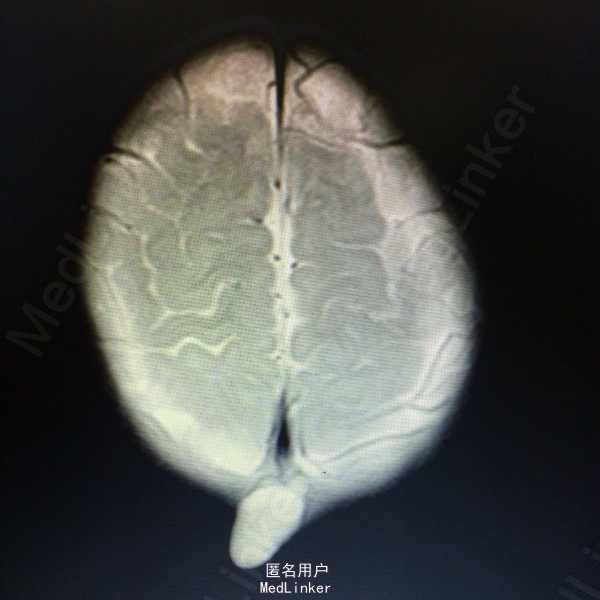

查体:枕后部肿物 辅助检查:行头颅MR提示顶针部中线异常信号,多考虑脑膜膨出

诊断:脑脊膜膨出 处理:枕部脑膜膨出囊切除术➕硬脑膜修补术

随访:病情缓解出院 讨论:脑脊膜膨出多为先天性疾病,该患儿7个月发病,脑组织从颅骨缺损口向外膨出犹如蕈状,故又有脑蕈之称(BrainFungus)。男性好发颅前部脑膨出,女性多见颅后部脑膨出,约占70%。神经系统症状轻者无明显神经系统症状,重者与发生的部位及受损的程度有关,可表现智力低下,抽搐及不同程度的瘫痪,腱反射亢进,不恒定的病理反射。